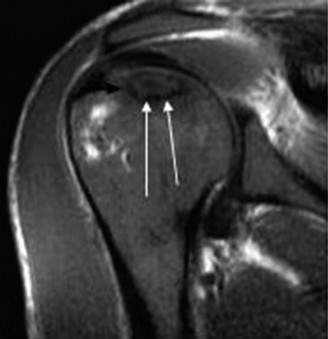

Magnetic Resonance Imaging (MRI) is the gold standard for early detection, staging, and volumetric assessment of the necrotic lesion. T1-weighted images typically demonstrate a well-demarcated band of low signal intensity separating the necrotic segment from viable bone. T2-weighted images may reveal the classic "double-line sign," representing the hypervascular granulation tissue interface at the border of the infarct. MRI is essential for identifying early, pre-radiographic Stage I disease, which is highly amenable to core decompression.